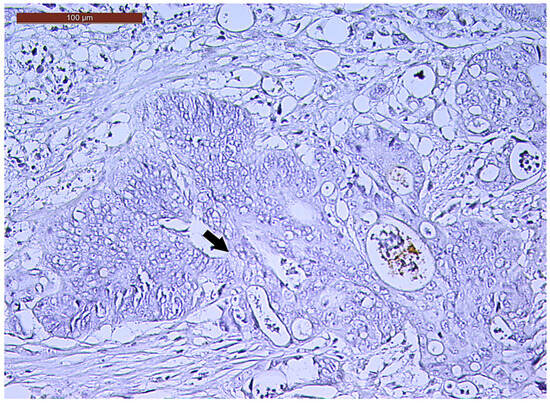

LVI was detected in 31 cases (51.7%), and perineural invasion (PnI) was identified in 20 cases (33.3%) (Figure 1 and Figure 2). EMVI and IMVI were registered in 31 (51.7%) and 21 cases (35%), respectively. Regarding Bd and PDC categories, a significant proportion of tumors were recorded as Bd1, while Bd2 was less common (49 cases; 81.6% vs. 7 cases; 11.7%) (Figure 3); moreover, a large proportion were classed as the PDC1 grade (Figure 4), while the PDC2 grade was less common (55 cases; 91.7% vs. 4 cases; 6.7%). The main clinicopathological characteristics of the study group are summarized in Table 4.

Figure 1. Lymphovascular invasion (arrow) in a ypT3-stage LARC case (H&E staining, 200×).